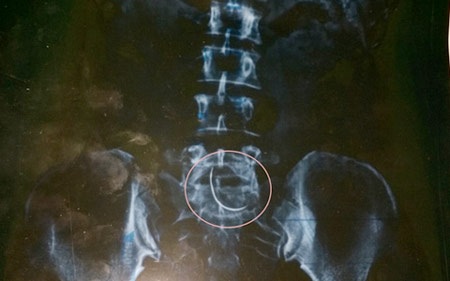

Thế nhưng, để chắc chắn, ngày 5/11, anh Tiến lại đưa vợ ra BVĐK Cửa Đông (TP Vinh, Nghệ An) kiểm tra. Nhận kết quả phim chụp từ tay bác sĩ, anh Tiến và chị Hòa không tin vào mắt mình, hình ảnh một chiếc kim cong vút nằm ở vùng bụng chị Hòa.

"Tôi thực sự không biết vì sao chiếc kim khâu lại nằm trong bụng mình. Hơn nữa nó lại nằm ở chỗ vết thương mà trước đây các bác sĩ tại BVĐK Can Lộc tiến hành mổ. Nhìn phim chụp mà tôi sởn gai ốc", chị Nguyễn Thị Hòa nhớ lại.

Chiếc kim đó cong cong như lưỡi câu cá, có độ dài chừng 3-5cm. Nghĩ tới đó thôi là cả người tôi ớn lạnh, chị Hòa rùng mình nói.